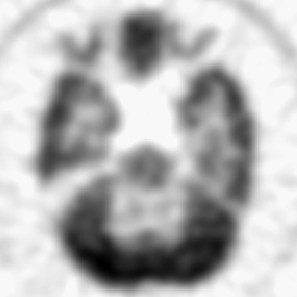

![]() |

| Reconstructed (upscaled by a factor of 4) RoI on union of shifted square lattice and its spectrum | |